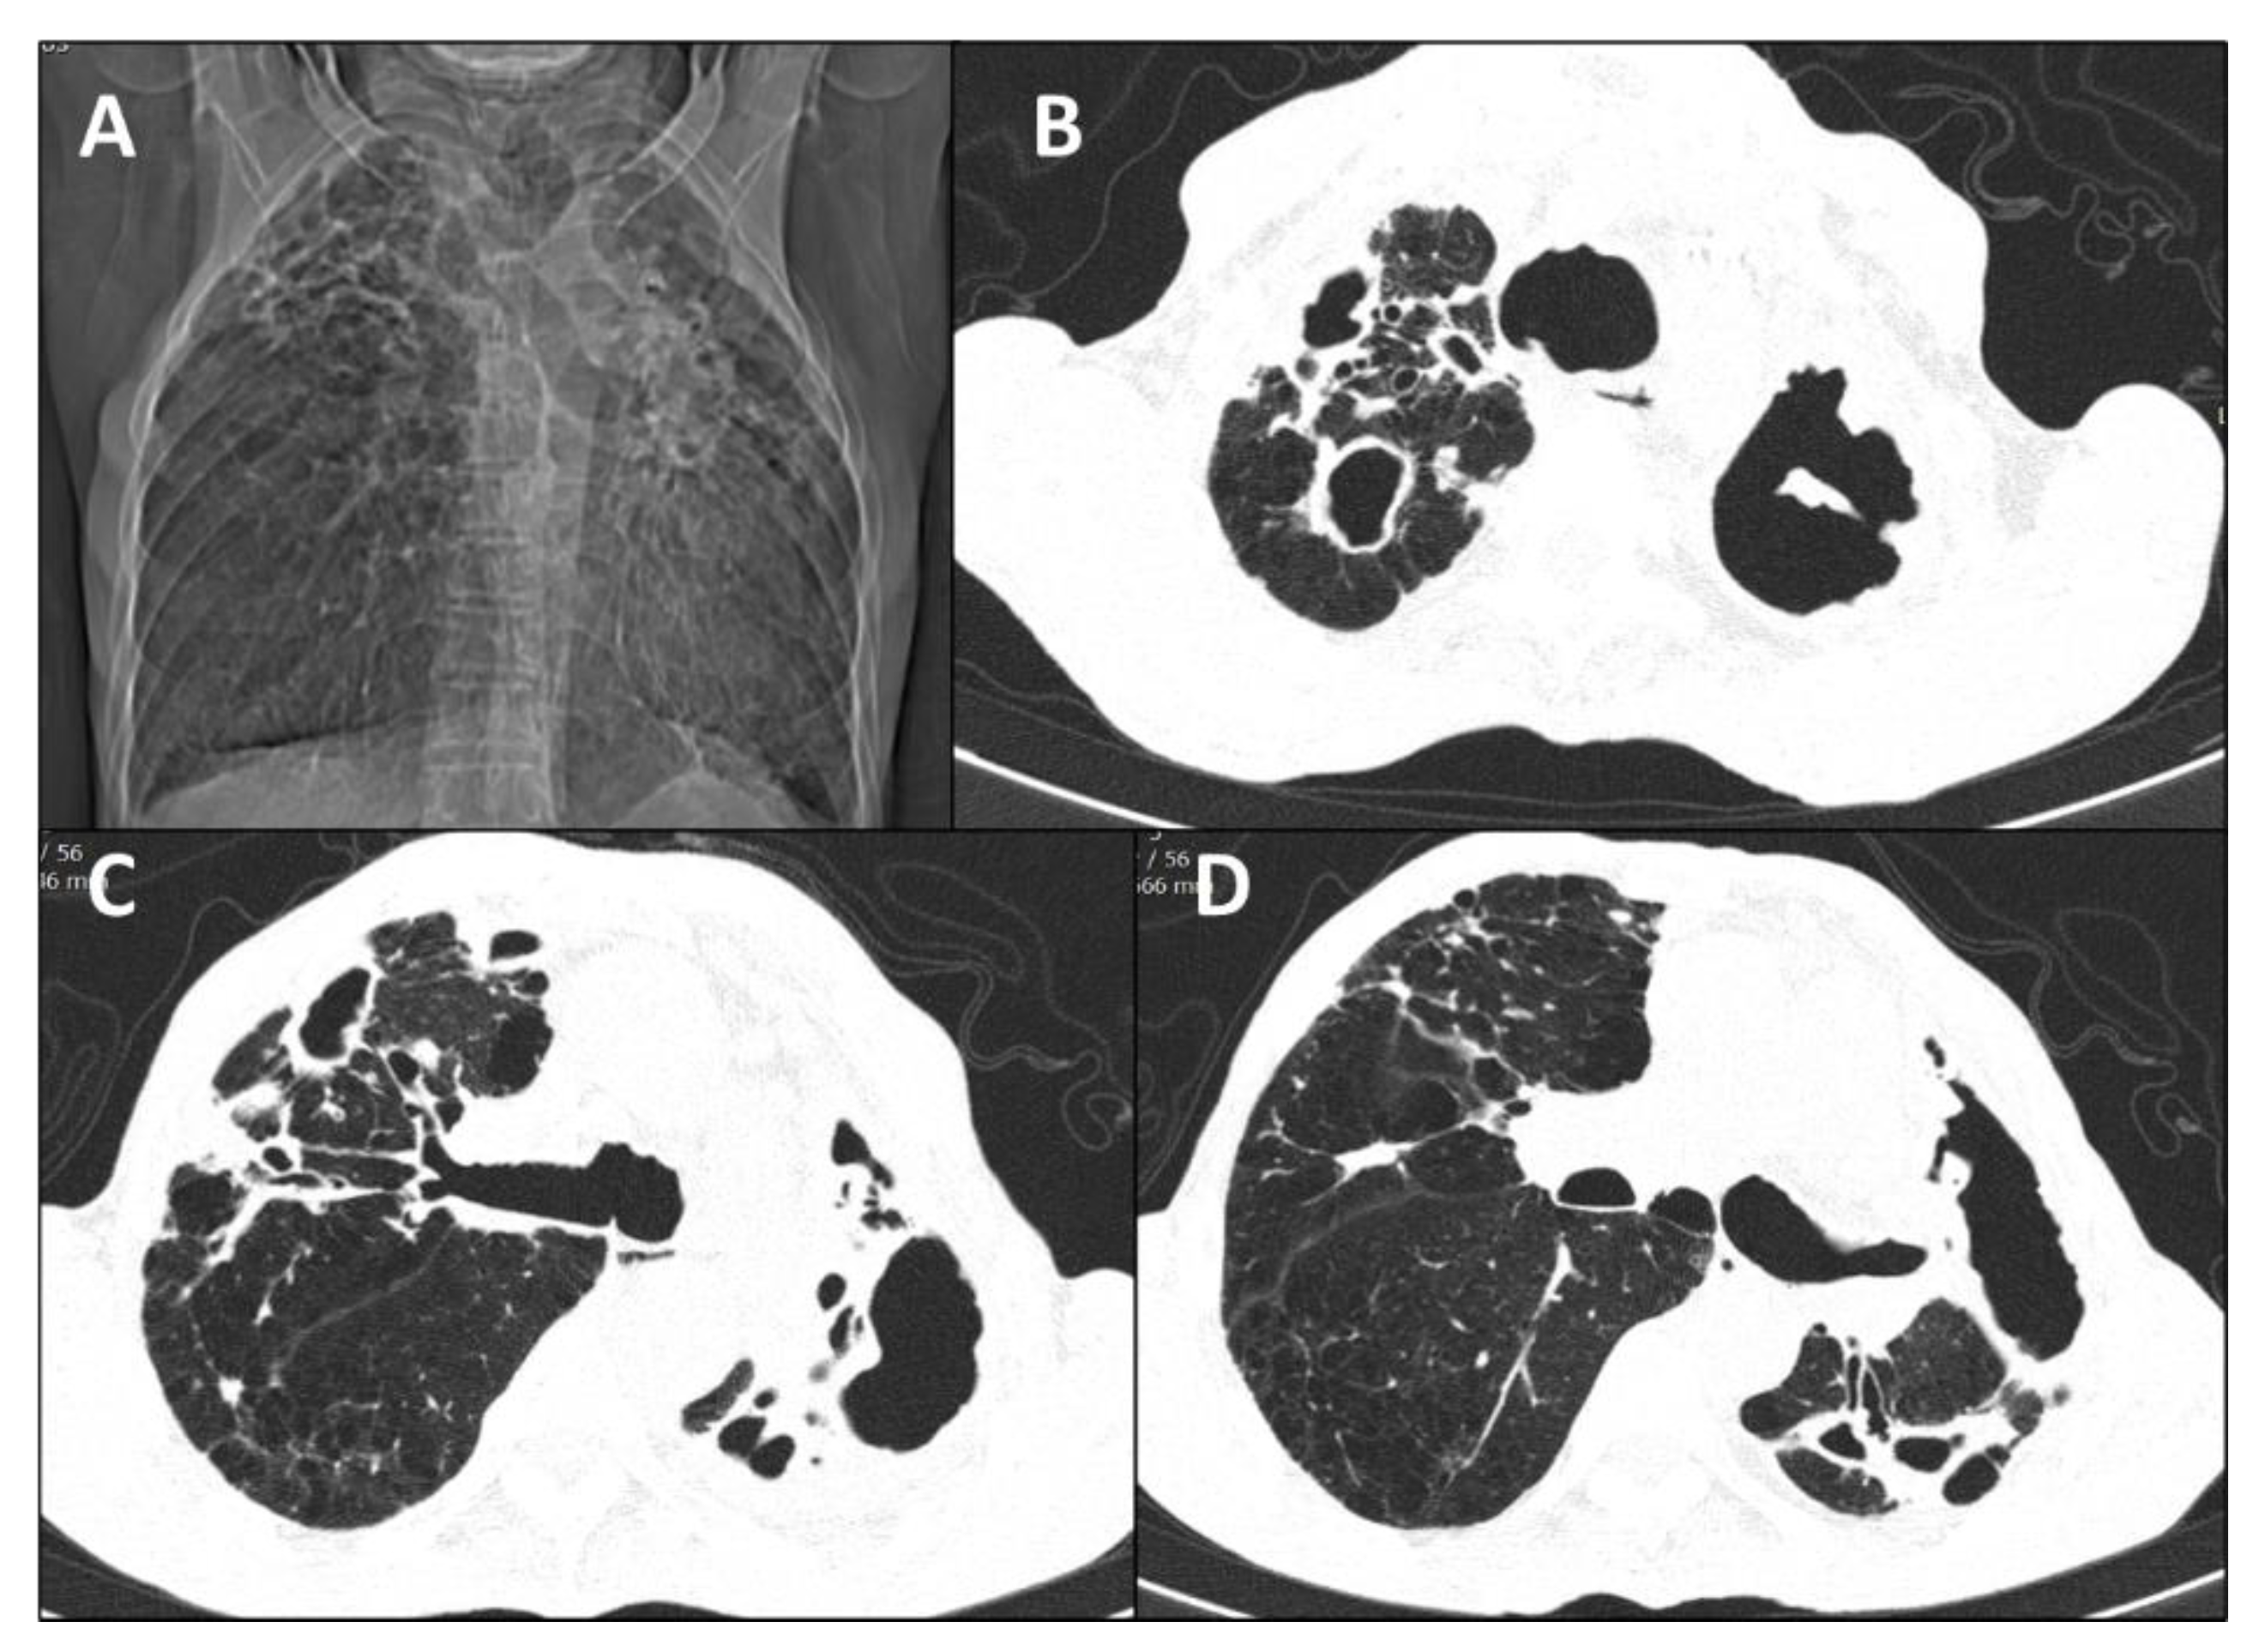

3.3. Radiological Patterns

| 1 (2018) | Male | 71 | None | Primary pulmonary | Lungs | Alcoholism COPD | No | Reticulonodular infiltrate; cavitation; fibrosis Unilateral/Multilobar | Sputum; BAL | ITZ; PSZ | Under treatment |

| 2 (2018) | Male | 63 | Contact with cat | Disseminated | Lungs, bone | Alcoholism COPD | No | Cavitation; fibrosis; hilar lymphadenopathy Unilateral/Unilobar | Sputum; BAL | ITZ; AmB; PSZ | Under treatment |

| 13 (2013) | Male | 43 | Scratched by diseased cat | Disseminated | Skin, bones, upper airways | HIV (CD4 = 35 cells/mm3) Alcoholism | Tuberculosis | Diffuse reticulonodular infiltrate; calcified nodules, fibrosis | Sputum | ITZ; TBF; AmB; PSZ | Death |

| 14 (2018) | Female | 20 | Contact with diseased cats | Disseminated | Skin, lungs, bones, upper airways | HIV (CD4 = 56 cells/mm3) Alcoholism | Pneumocystis pneumonia | Cavitation; reticulonodular infiltrate; consolidation | Sputum | ITZ; AmB; PSZ | Cure |